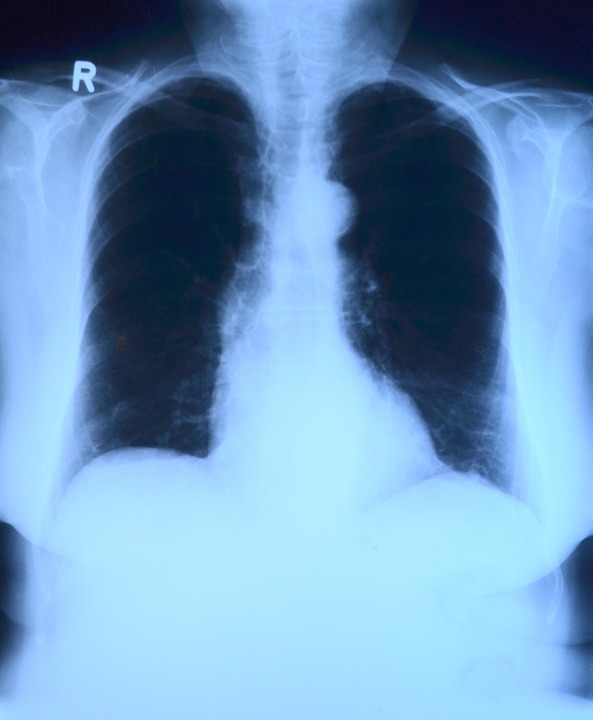

В Сызрани медучреждение получило уникальное медицинское оборудование. Речь идет о рентген-аппарате «УниЭксперт», который уже работает в новом инфекционном корпусе ЦГРБ. Здесь открыли круглосуточный рентген-кабинет, где будут выполнять рентгенологические исследования, в том числе и рентгенографию легких.

Обследование пациентов инфекционного профиля отдельно необходимо для разграничения потоков пациентов. Пациенты инфекционного профиля, нуждающиеся в проведении рентгенологического исследования, проходят обследование в приемном покое инфекционного корпуса на новом рентген-аппарате без необходимости их транспортировки в другие учреждения, — пояснила заведующая инфекционным отделением Татьяна Павлова.